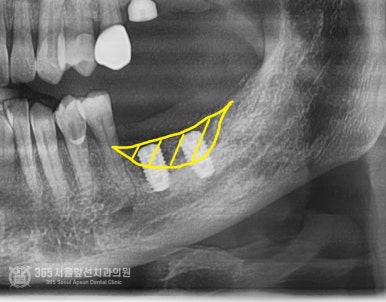

촬영일시: 2024.07.07. 제거하고 대략 2개월 정도 지나고 엑스레이입니다. 뼈가 움푹 파여서 이 상태로는 임플란트 식립이 어려운 상황입니다. 촬영일시: 2024.08.10. 골이식과 동시에 임플란트를 식립하였고 사진의 노란색 부위만큼이 골이식이 들어간 부위입니다. 이 환자분의 증례에서 시행된 골이식술은 수직골증강술이라는 매우 고난이도 술식입니다. 하지만 숙련된 의료진과 함께라면 걱정안하셔도 되겠습니다 ㅎㅎ 촬영일시: 2024.10.10. 약 5개월 정도 지난 후 잇몸을 열어서 이식된 골이 잘형성되었는지 확인함과 동시에 임플란트도 뼈와 잘결합되었는지 확인합니다. 다행히 뼈 형성도 좋고, 임플란트도 단단하게 잘 붙었습니다 ㅎㅎ